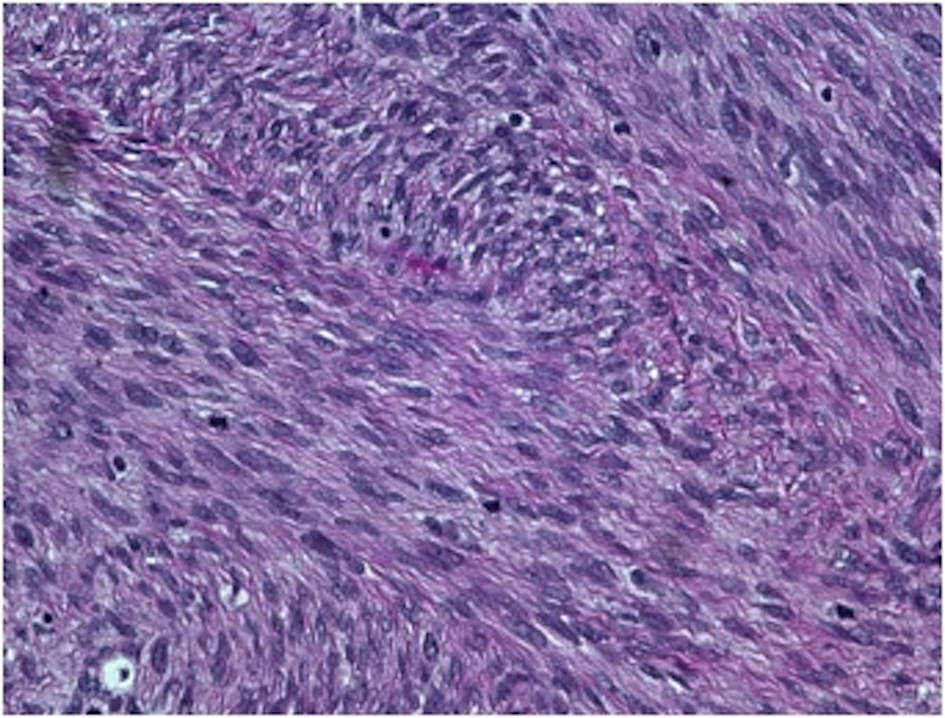

On gross examination, the biopsy specimen had a shiny appearance suggesting myxoidal features along with other areas of hemorrhage (Fig. 4). On histopathological examination (Fig. 5, 6), the specimen again revealed myxoidal features with small round blue cells and other areas of spindle cells arranged in a wavy streamline pattern. There were also areas of high mitotic activity. Histochemically, the specimen stained positive for vimentin and CD99. It stained diffusely positive for S100 and had patchy staining for NSE. It stained negatively for CD31, CD34, desmin, melan-A, SMA, pan-keratin, EMA, CD45, CD56, chromogranin, and synaptophysin.

![]() Click for large image | Figure 5. 20 × view with spindle cells and areas with loose and dense matrix of small round blue cells. |

![]() Click for large image | Figure 6. 40 × view with small round blue cells as well as spindle cells arranged in a wavy fasicular pattern suggestive of neural origin. |

On microscopic examination, ES/PNET and MPNST also show similar patterns. MPNSTs themselves have variable differentiation, such as rhabdomyoblastic differentiation, glandular malignant differentiation, malignant triton tumor, epithelioid malignant shwannoma, and superficial epithelioid differentiation. In general, however, MPNSTs are marked by intermixed dense cellular fasicles and myxoid regions (marbleized pattern) with round or fusiform cells [2]. There may also be varying degrees of mitosis, necrosis, and calcification [10]. Similarly, ES/PNETs show round small cells arranged in sheets, lobules, and rosettes [1]. In a series of 120 MPNST cases, Ducatman et al notes that only a small percentage of the MPNST cases showed typical Schwannian differentiation including cellular palisading, heterologous elements, and a wavy, cytoplasmic, nuclear configuration [3].